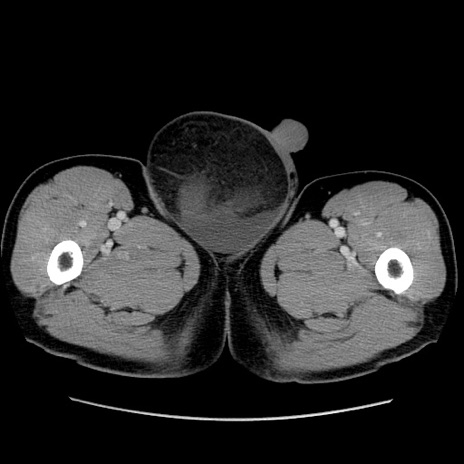

症例34(横断像)

【症例】60歳代 男性

【主訴】右鼠径部膨隆

【現病歴】1年程前より右鼠径部膨隆あり。自己にて還納可能だったため放置していた。3時間前より右鼠径部の脱出を認め、還納困難となり受診。

【身体所見】右鼠径部に小児頭大の膨隆あり。弾性硬であり、用手還納は困難。左鼠径部にも膨隆を認める。脱出はなし。